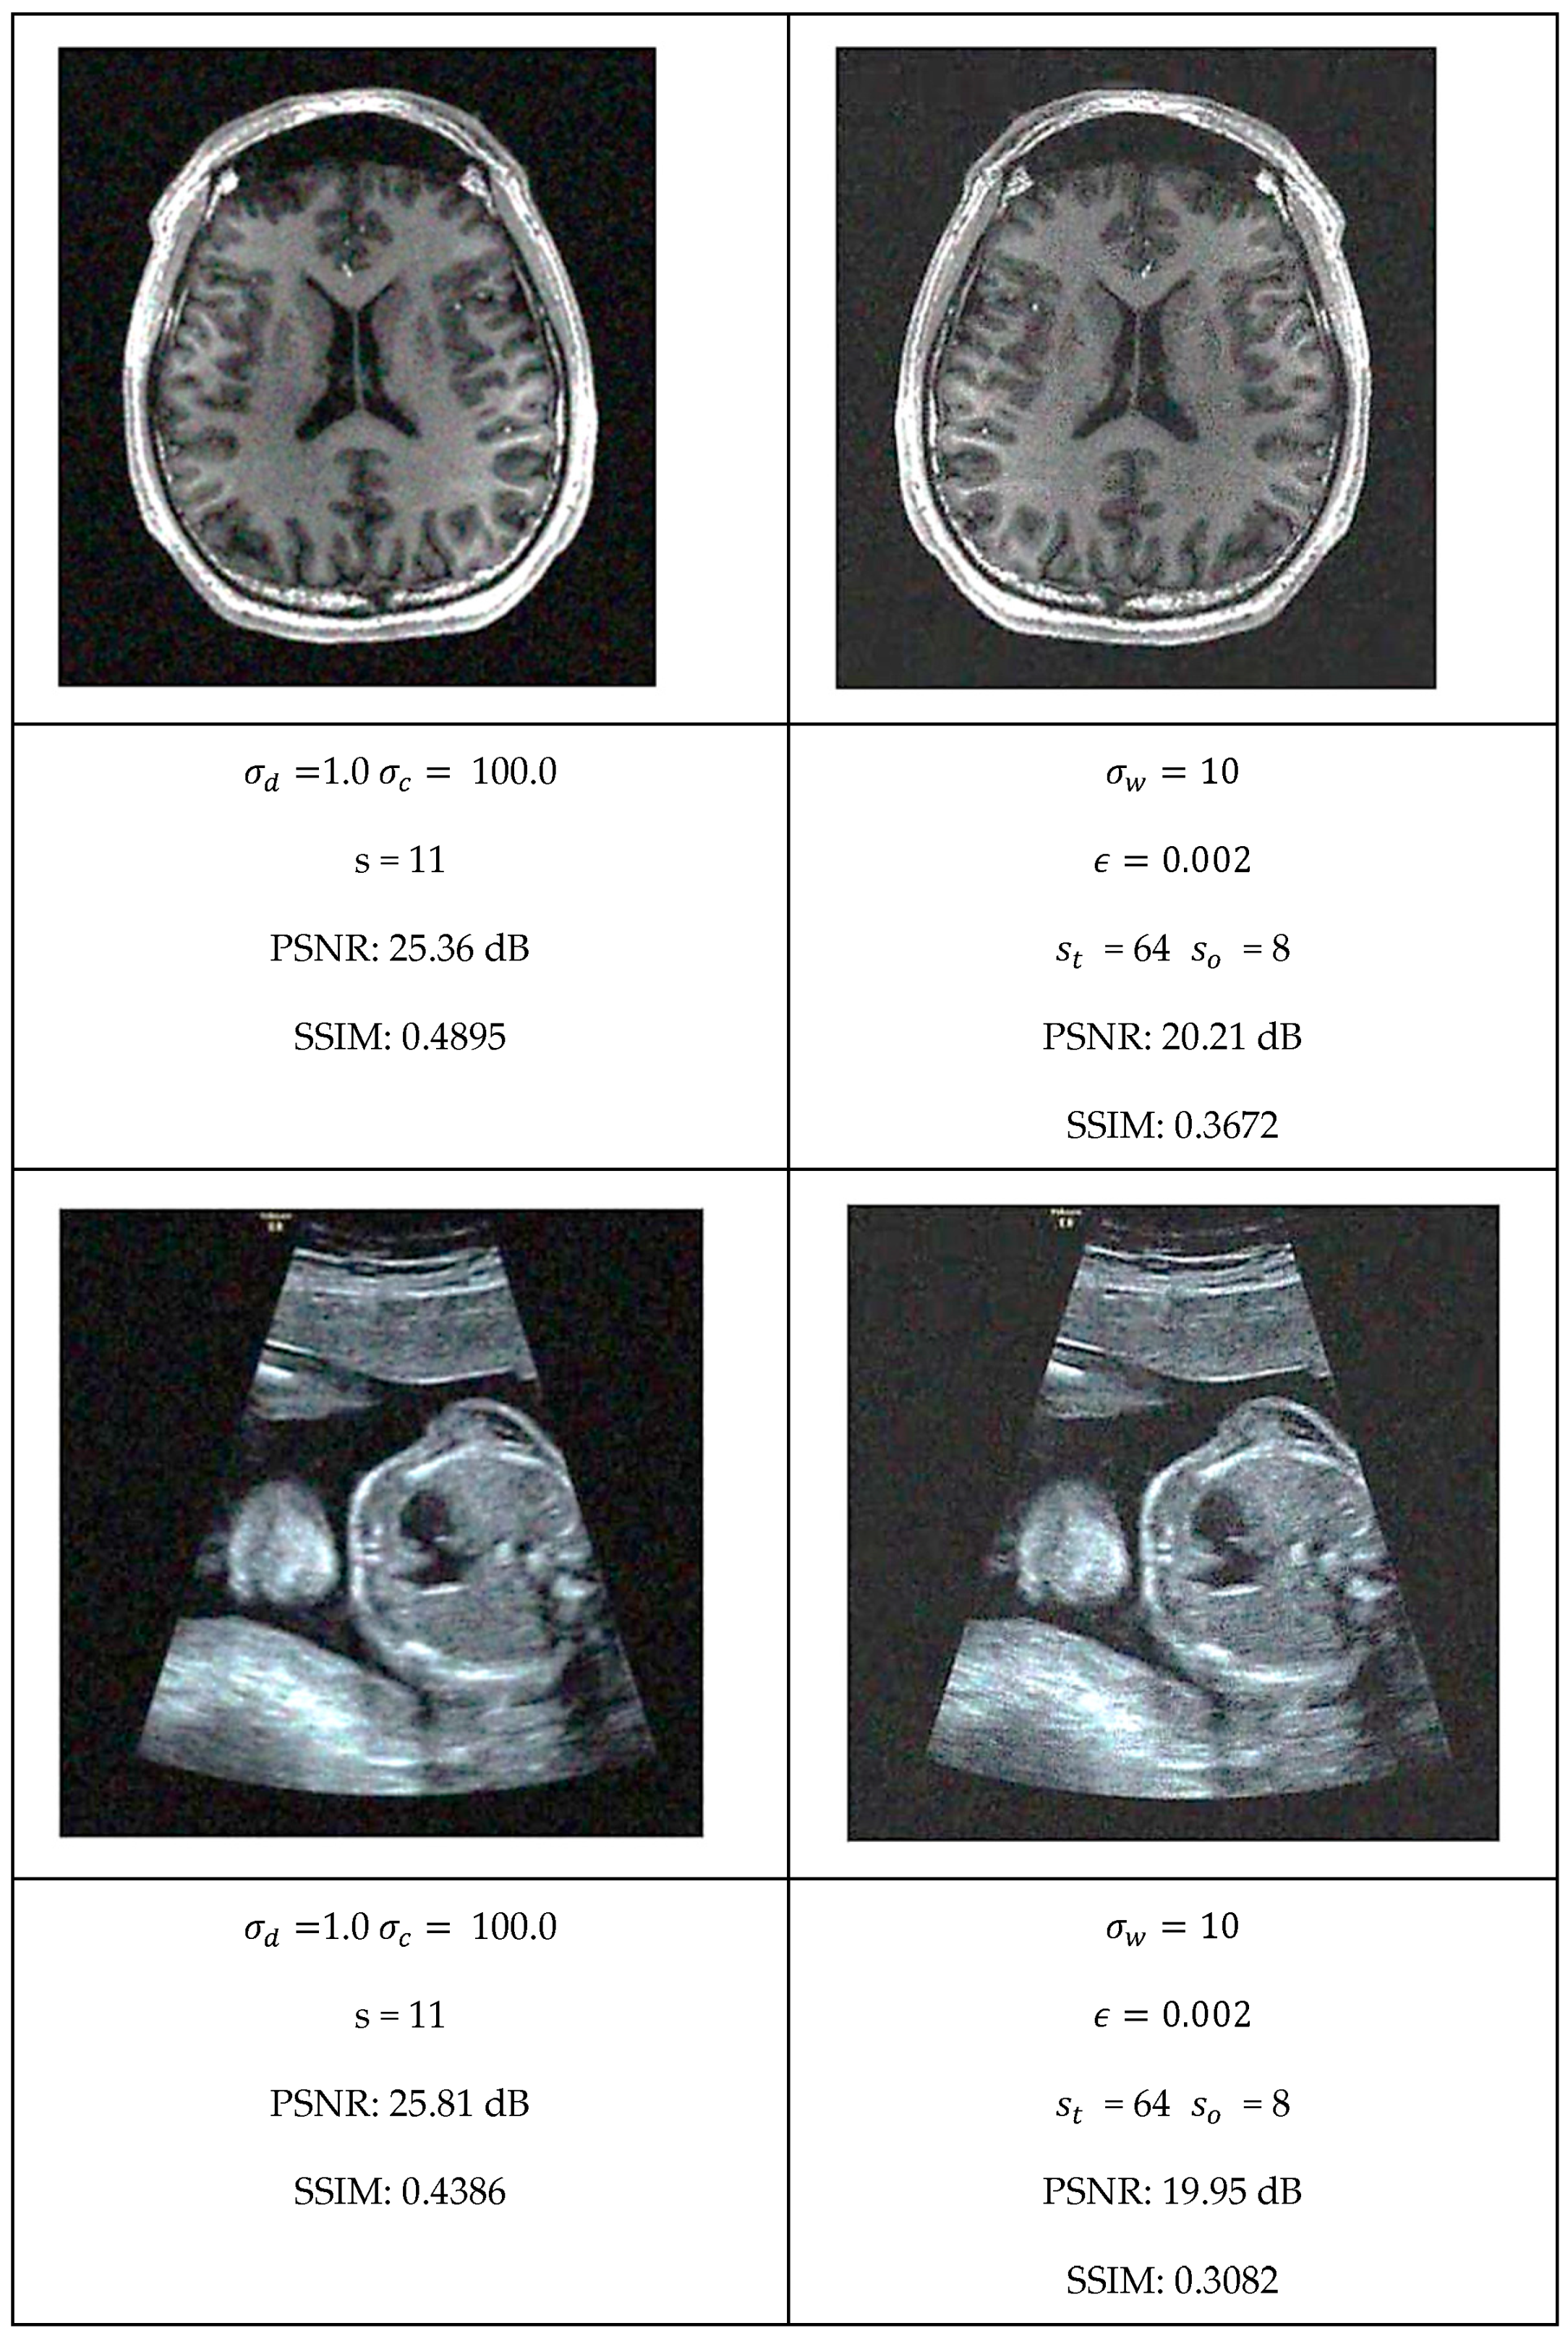

This section presents a comprehensive comparative analysis of our geodesic filtering approach against the state-of-the-art methods. The key to this comparison is based on PSNR and SSIM difference metrics. The noisy images shown in Figure 8 were processed using various implementations of the filtering algorithms described in Section 2. To be fair in our comparison, as with the geodesic filter, we tuned the parameters to produce the best PSNR value possible. The results of this comparison are collected in Figure 9 and Figure 10.

Figure 10.

Optimal filtering results for bilateral and GW-DIP algorithms.

Each algorithm was carefully tuned to achieve optimal performance using the same test image database with standardized noise conditions. For each filter, the tuning parameters are as follows:

- Bilateral Filter: kernel size, spatial distance weight, and color distance weight;

- Gaussian Weighted Wavelet DIP Neural Network: Gaussian variance, minimum tile loss, tile size, and tile overlap size.